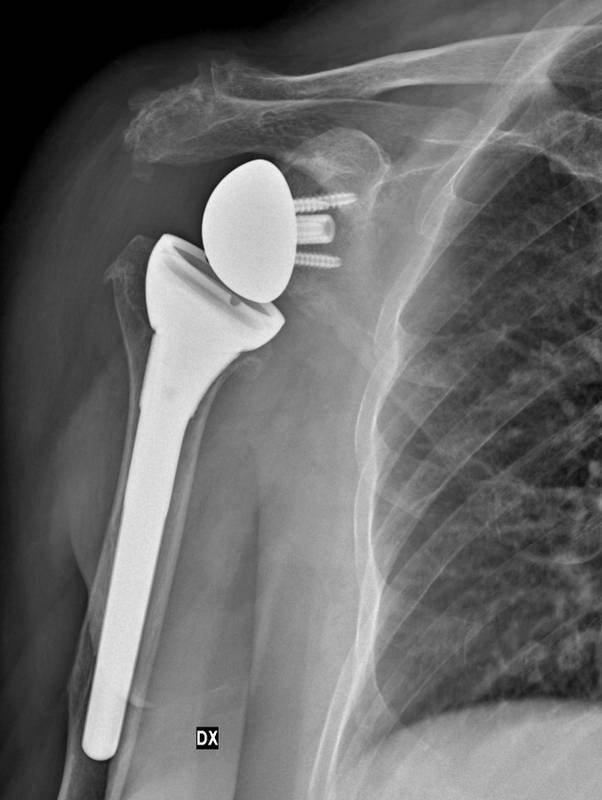

Sandrina. Protesi di spalla su lesione non riparabile di cuffia dei rotatori

Signora Sandrina, artrosi spalla su lesione cuffia non riparabile

Le viene proposto un intervento di protesi inversa alla spalla. La funzione di questa protesi si basa sull’azione del solo muscolo deltoide, rendendo possibile una discreta funzionalità della spalla anche in pazienti con lesione non riparabile di tutti i tendini della cuffia dei rotatori, come nel caso della signora Sandrina.